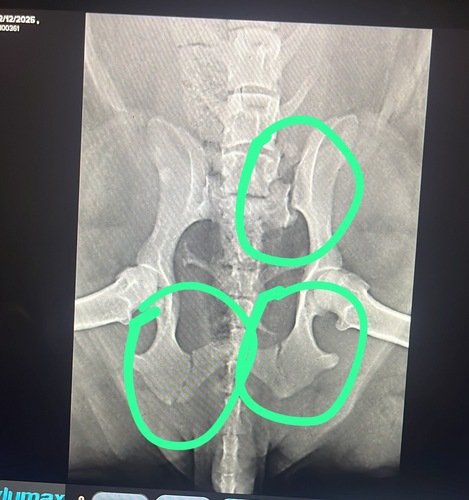

Eu sou a Bella Nutella Soares e, no último domingo (21/12), enquanto aproveitava meu passeio matinal, fui atacada por um doguinho de rua. Infelizmente, isso resultou em uma fratura no quadril, e agora estou com dificuldade para andar e sentindo dor.

Após os exames, a veterinária recomendou uma cirurgia de urgência para que eu possa me recuperar e voltar a brincar sem dor. Minha família está precisando de apoio financeiro nesse momento, e o carinho de todos é o que mais importa.